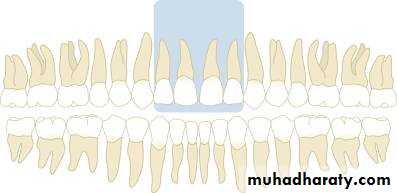

Maxillary incisor region

Maxillary canine region

Maxillary premolar region

Maxillary molar region

Mandibular incisor region

Mandibular canine region

Mandibular premolar region

Mandibular molar region